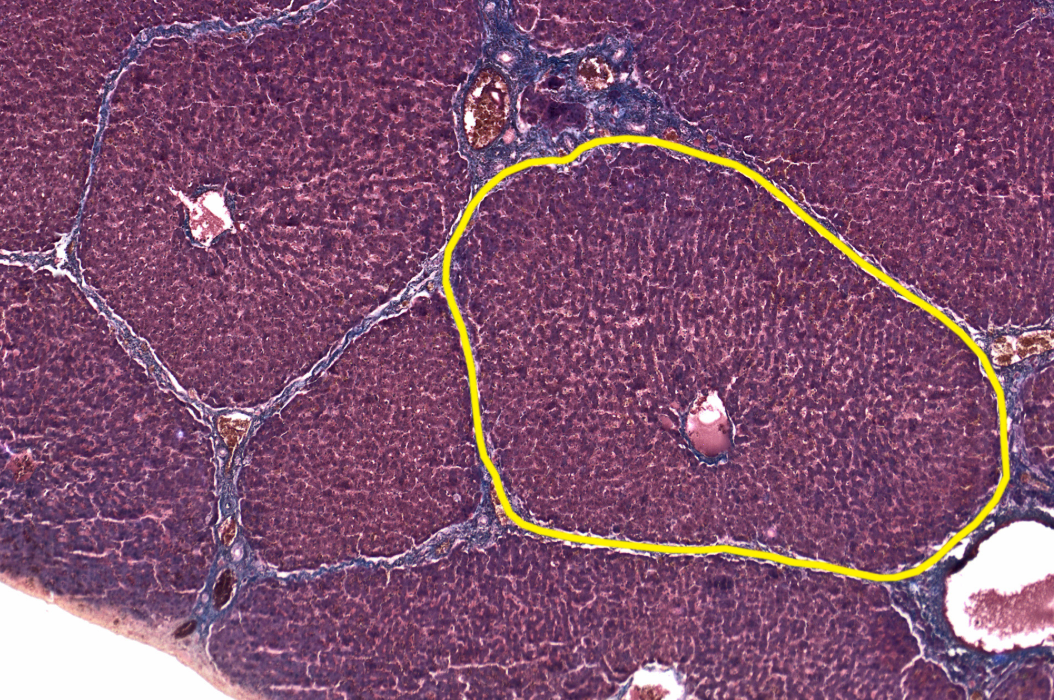

Liver

NOTICE: THE TIGHTLY PACKED HEPATOCYTES FORMING THE UNIQUE HEXAGONAL SHAPE OF THE LOBULES AND THE LIVER SINUSOIDS THAT SUPPLY THEM WITH NUTRIENTS